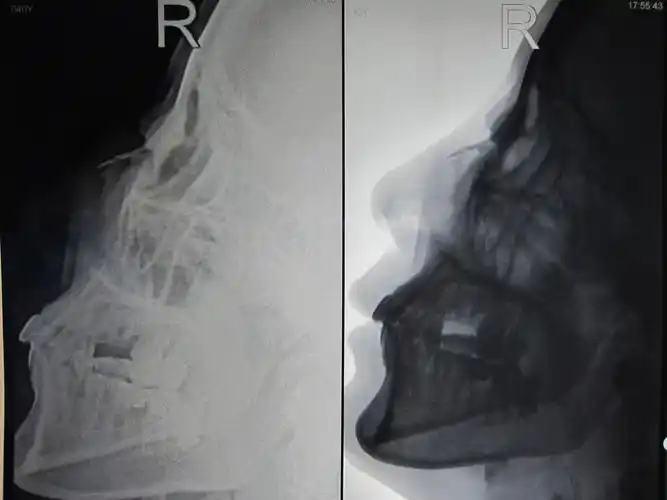

鼻骨骨折发病位置是头和鼻子,病因是鼻部遭受拳击,运动外伤

外伤致鼻骨骨折,颜面部皮肤软组织肿胀(附检查单,ct,x片).

鼻骨骨折

本人学生有个鼻骨骨折帮忙老师们看下伤到什么程度